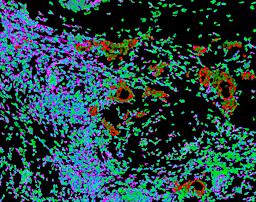

Pancreatic ductal adenocarcinoma is a lethal disease with limited treatment options and poor survival. We studied 83 spatial samples from 31 patients (11 treatment-naïve and 20 treated) using single-cell/nucleus RNA sequencing, bulk-proteogenomics, spatial transcriptomics and cellular imaging. Subpopulations of tumor cells exhibited signatures of proliferation, KRAS signaling, cell stress and epithelial-to-mesenchymal transition. Mapping mutations and copy number events distinguished tumor populations from normal and transitional cells, including acinar-to-ductal metaplasia and pancreatic intraepithelial neoplasia. Pathology-assisted deconvolution of spatial transcriptomic data identified tumor and transitional subpopulations with distinct histological features. We showed coordinated expression of TIGIT in exhausted and regulatory T cells and Nectin in tumor cells. Chemo-resistant samples contain a threefold enrichment of inflammatory cancer-associated fibroblasts that upregulate metallothioneins. Our study reveals a deeper understanding of the intricate substructure of pancreatic ductal adenocarcinoma tumors that could help improve therapy for patients with this disease.